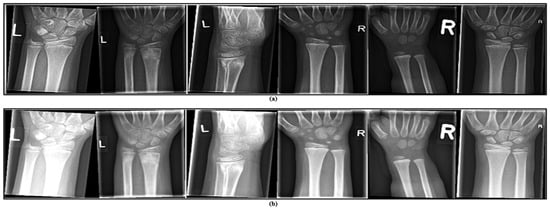

- This dataset is general, containing 20,327 labelled and categorized images, and is ideal for developing and testing computer vision models.

- The dataset includes a wide variety of images capturing early bone development in children.

- Reviewing wrist development at this stage provides important insights for identifying, managing, and preventing abnormalities that might not be noticeable in adult wrists.